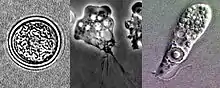

تتواجد نيجلرية دجاجية بثلاثة أشكال هي: كيسة، أتروفة، سوطيات، أما في الإنسان لا يوجد بشكله كيسة لكن يوجد بأشكاله الأخرى وبالأغلب أتروفة.

مرحلة كيسة

هذه المرحلة تتكون عندما يصبح الكائن في ظروف غير طبيعية مثل الجفاف ونقص الغذاء وانخفاض درجات الحرارة ووجود أعداد كبيرة منه.

مرحلة الأتروفة

هي مرحلة التكاثر للكائن، على درجة حرارة أعلى من 25 °C، ويكون النمو سريعاً عند 44 °C، وطريقة التكاثر لاجنسي بالانقسام الثنائي. وتتميز الأوتروفة بنواتها والهالة المحيطة بها.وتنتقل بالأقدام الكاذبة، وتتغذى على البكتيريا وهي في خارج العائل، لكن داخل الإنسان أو العائل تتغذى على خلايا الدم الحمراء وخلايا الدم البيضاء عن طريقة عملية البلعمة.

مرحلة السوطية

تتكون النيجلرية إلى هذا الشكل بعد تحولها من الأتروفة ويحدث ذلك عند التغير في التركيز الأيوني، مثل وضع الكائن بماء مقطر لعدة ساعات.